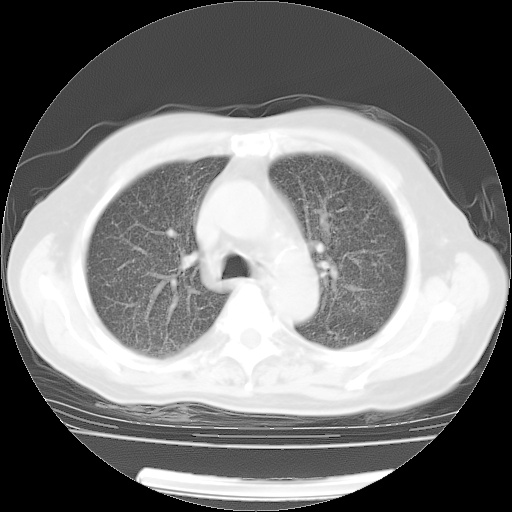

4月14日肺部CT

楼主| 发表于 2010-4-28 16:51 | 显示全部楼层

楼主| 发表于 2010-4-28 16:53 | 显示全部楼层

肺部CT平扫未见异常。